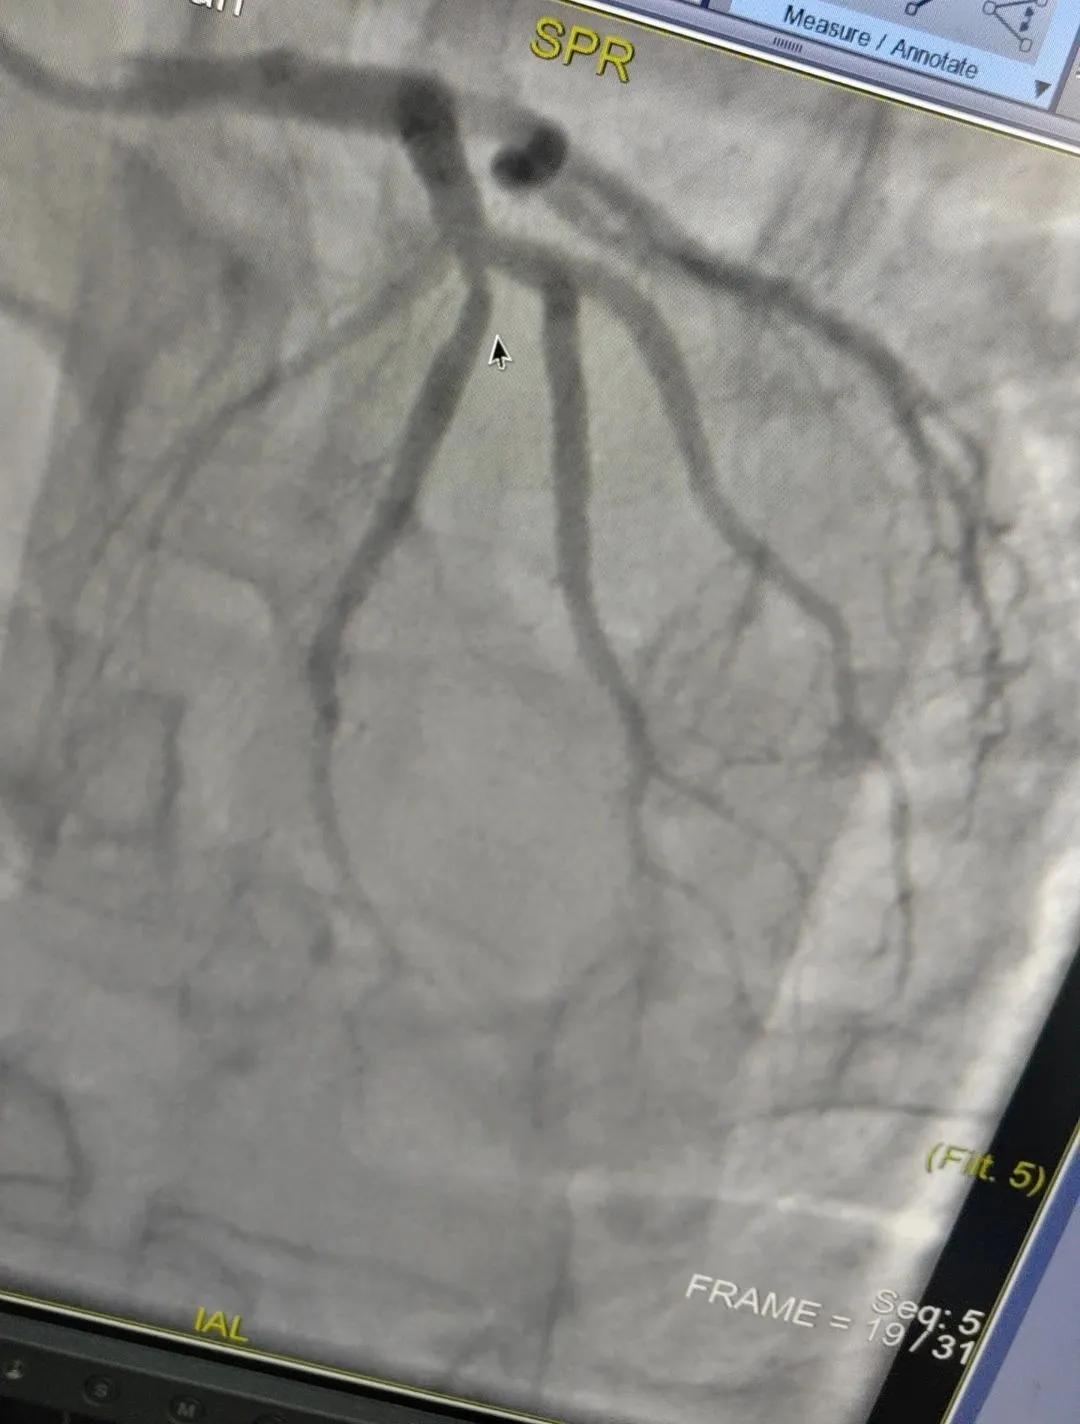

術(shù)中心血管造影顯示:LAD中段發(fā)出D1處可見約50%節(jié)段性狹窄,RCA中段狹窄約40%,PLA可見約70%狹窄病變。

腦血管造影顯示:左側(cè)頸內(nèi)動脈嚴(yán)重遷曲,左側(cè)大腦前動脈未顯影,左側(cè)大腦中動脈M1中段以遠(yuǎn)未顯影,M1近段串珠樣嚴(yán)重狹窄,顱底可見少量煙霧血管,后交通動脈未開放;右側(cè)頸內(nèi)動脈嚴(yán)重遷曲。右側(cè)大腦前動脈A1段嚴(yán)重遷曲。

心腦聯(lián)合造影不僅明確患者的病因和病變血管,還為下一步治療提供了有力的依據(jù)。